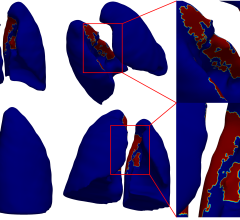

Even before the pandemic began to spread, the idea of offering radiologists the flexibility to work from home was trending. When COVID-19 enforced social distancing and new work behavior, it kicked this trend into high gear. Working from home helps limit exposure to the virus while still allowing radiologists to read as if they were on-site. The first challenge is creating home reading solutions that are the same level of quality, security and performance radiologists get from a medical workstation in the hospital reading room. The second challenge is getting them set up in a timely manner.

The VisionTek Thunderbolt 3 Mini eGFX Enclosure comes in a sleek and portable design that discretely sits on a desk, or hidden away, to handle graphic intensive medical scan applications. Combined with a pre-installed Barco MXRT-display controller, VisionTek’s Thunderbolt 3 Mini eGFX Enclosure can accelerate the most demanding medical scan software programs.

"VisionTek’s Mini eGFX enclosure powered by Barco MXRT series graphics boards and diagnostic displays allow Radiologists to remotely read scans in the safety of their home office." stated Michael Innes, President, VisionTek Products, LLC. “VisionTek is very proud to play a small part in technology innovation that impacts some of the most critical healthcare applications within the radiology community.”